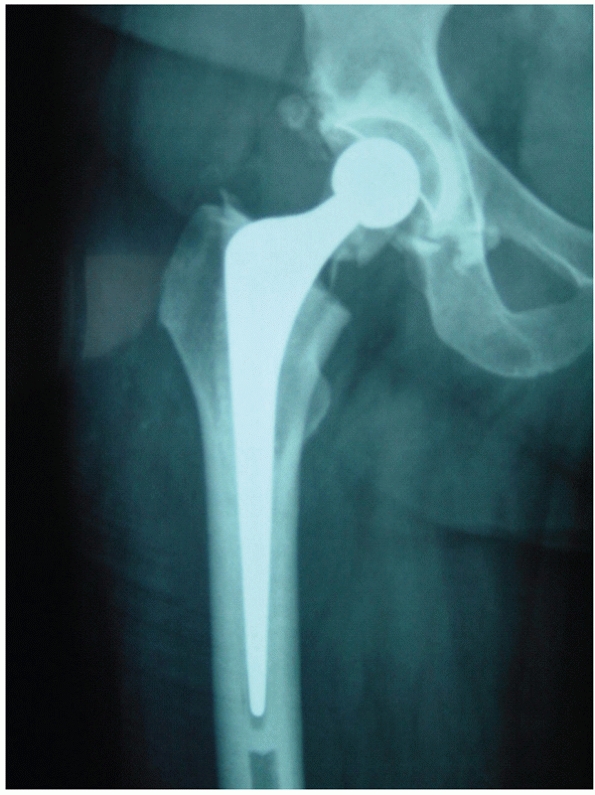

![]() |

|

FIGURE 47-2 A 78-year-old patient presented with painful left hip after a fall. There was no fracture clearly visible on the AP (A) or lateral (B) radiographs. A transverse MRI scan (C) showed a haemarthrosis of the left hip joint and AP MRI images showed an undisplaced intracapsular hip fracture (D,E).

is probably the most useful additional form of imaging in modern

practice (Fig. 47-2). It has been shown to be more accurate than a bone scan75,92,208 in the early stages after injury and there is no radiation.177

It also picks up soft tissue problems that may be causing hip pain in

the absence of a fracture. Nonetheless for the majority of patients

plain radiographs are adequate for clinical decision making.